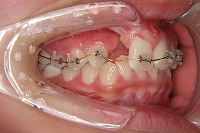

反対咬合を主訴に来院された、右側唇顎裂の10歳6ヵ月の女の子です。診断「右側唇顎口蓋裂で反対咬合を伴う」1期治療で反対咬合の解消と上顎の前歯の並びを修正しました。2期治療は抜歯をせず治療を行いました。